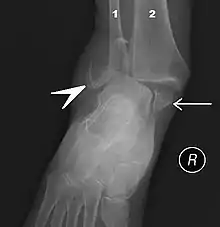

Fracture of both sides of the ankle with dislocation as seen on anteroposterior X-ray. (1) fibula, (2) tibia, (arrow) medial malleolus, (arrowhead) lateral malleolus

An ankle fracture is a break of one or more of the bones that make up the ankle joint.[20] Symptoms may include pain, swelling, bruising, and an inability to walk on the injured leg.[20] Complications may include an associated high ankle sprain, compartment syndrome, stiffness, malunion, and post-traumatic arthritis.[20][21]

Ankle fractures may result from excessive stress on the joint such as from rolling an ankle or from blunt trauma.[20][21] Types of ankle fractures include lateral malleolus, medial malleolus, posterior malleolus, bimalleolar, and trimalleolar fractures.[20] The Ottawa ankle rule can help determine the need for X-rays.[21] Special X-ray views called stress views help determine whether an ankle fracture is unstable.